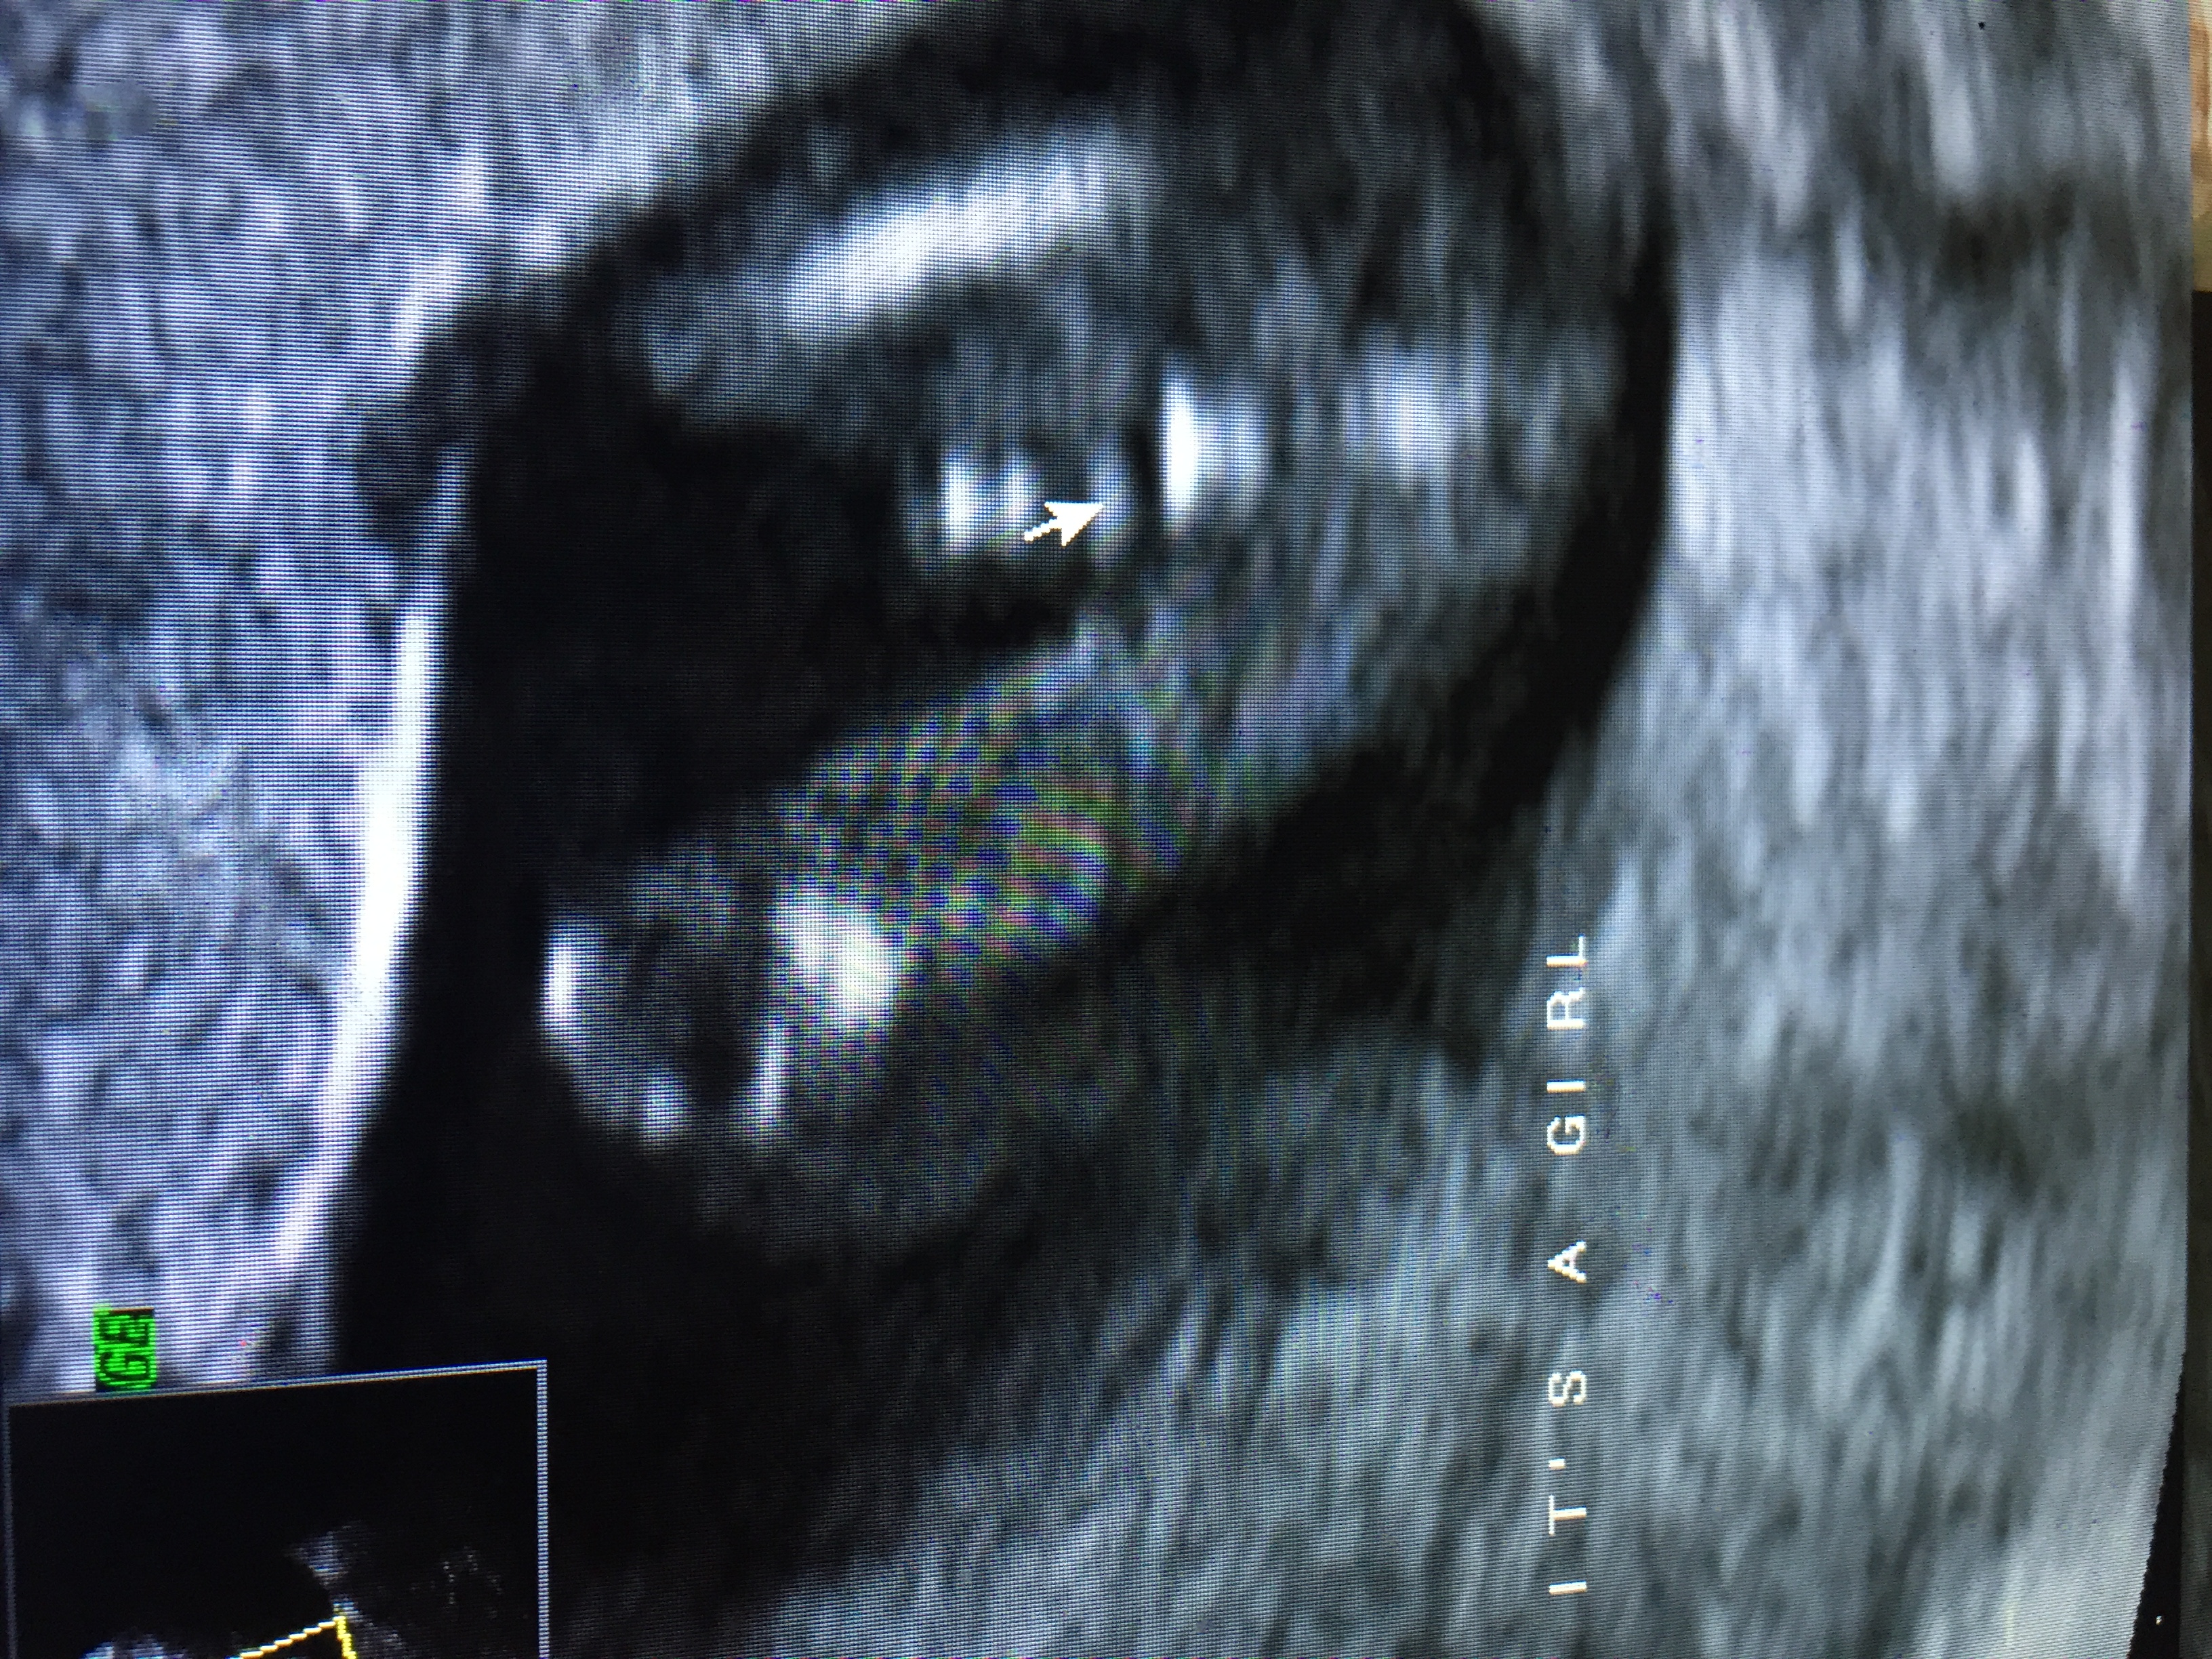

• I went in for a 14 1/2 week gender ultrasound and they told me girl and wrote it's a girl! All over the pictures. She gave me this one below and explained that the line between the babies bottom and umbilical cord means girl. 12 weeks seems pretty early to be able to tell